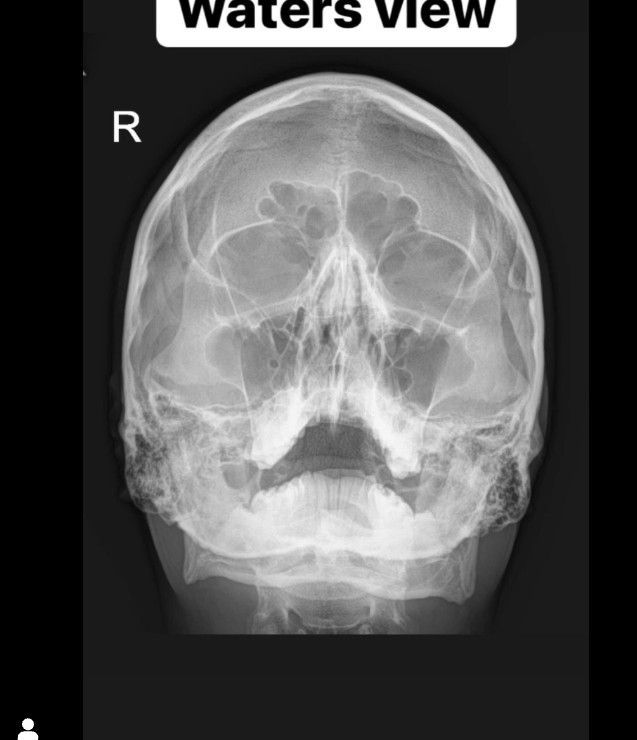

Waters' view is a radiographic view of the skull. It is commonly used to get a better view of the maxillary sinuses. An x-ray beam is angled at 45° to the orbitomeatal line. The rays pass from behind the head and are perpendicular to the radiographic plate.